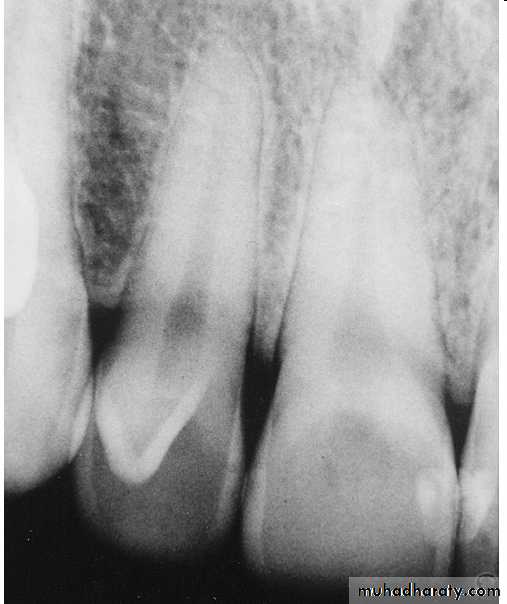

Radiographically:

Bulbous crownsCervical constriction

Thin roots

Early obliteration of roots canals & pulp chambers.

Radiographically (Type I& II ):

partial or total obliteration of pulp chambers & root canals by continued formation of dentin.

roots may be short & blunted.

Normal cementum, periodontal membrane & bone .